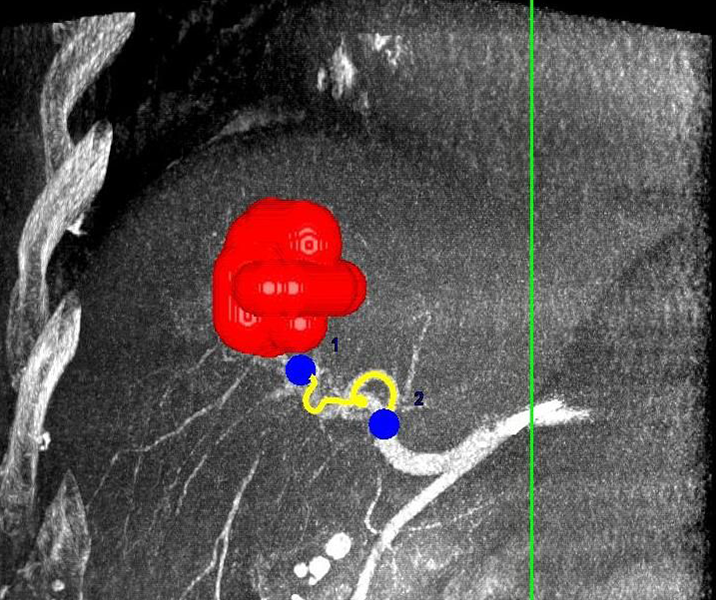

Eine Voraussetzung für die vollständige chirurgische Entfernung von Knochen- und Weichteiltumoren ist die präzise Erkennung der Tumorausdehnung und der Tumorgrenzen. Mit der Kernspintomographie (MRT) kann das Tumorgewebe exzellent von gesundem Gewebe abgegrenzt werden und somit die Ausdehnung vor der Operation bestimmt werden. Nach der kernspintomographischen Bestimmung der Tumorausdehnung werden unter kontinuierlicher MRT-Bildgebung die Grenzen des Tumors markiert. Die Marker werden mit einer Nadel ins angrenzende gesunde Gewebe eingebracht. Die Markierung kann am Tage vor der Operation durchgeführt werden. Alternativ ist die Tumormarkierung auch mit anderen bildgebenden Verfahren möglich, z.B. mit der Computertomographie oder dem Ultraschall.

Abbildung: Bei diesem Patienten wurde ein im Röntgen nur schlecht sichtbarer Knochentumor vor der Operation unter MRT-Kontrolle mit kleinen röntgendichten Spiralen („Coils“) markiert. Damit hat der Operateur eine optimale Darstellung des Tumorbereichs bzw. der Tumorgrenzen und kann gezielter, schonender und effektiver operieren.